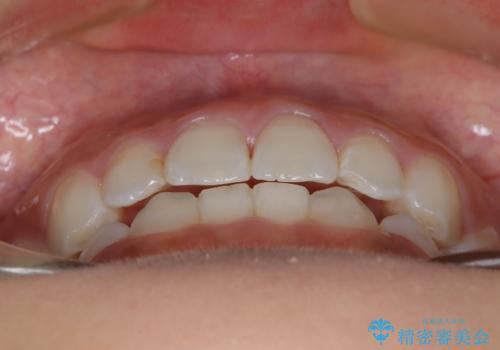

- 子供のころに矯正治療をされていたが、後戻りをしてしまったという20代女性の患者様です。上顎左右の2番が、咬合時に下顎の歯よりも内側に入っているクロスバイトという状態でした。奥歯の咬合関係は変えずに、マウスピース矯正にて前歯の並びを綺麗なアーチに仕上げました。再度後戻りしてしまうリスクを軽減させるために、リテーナー(保定装置)をお渡ししています。